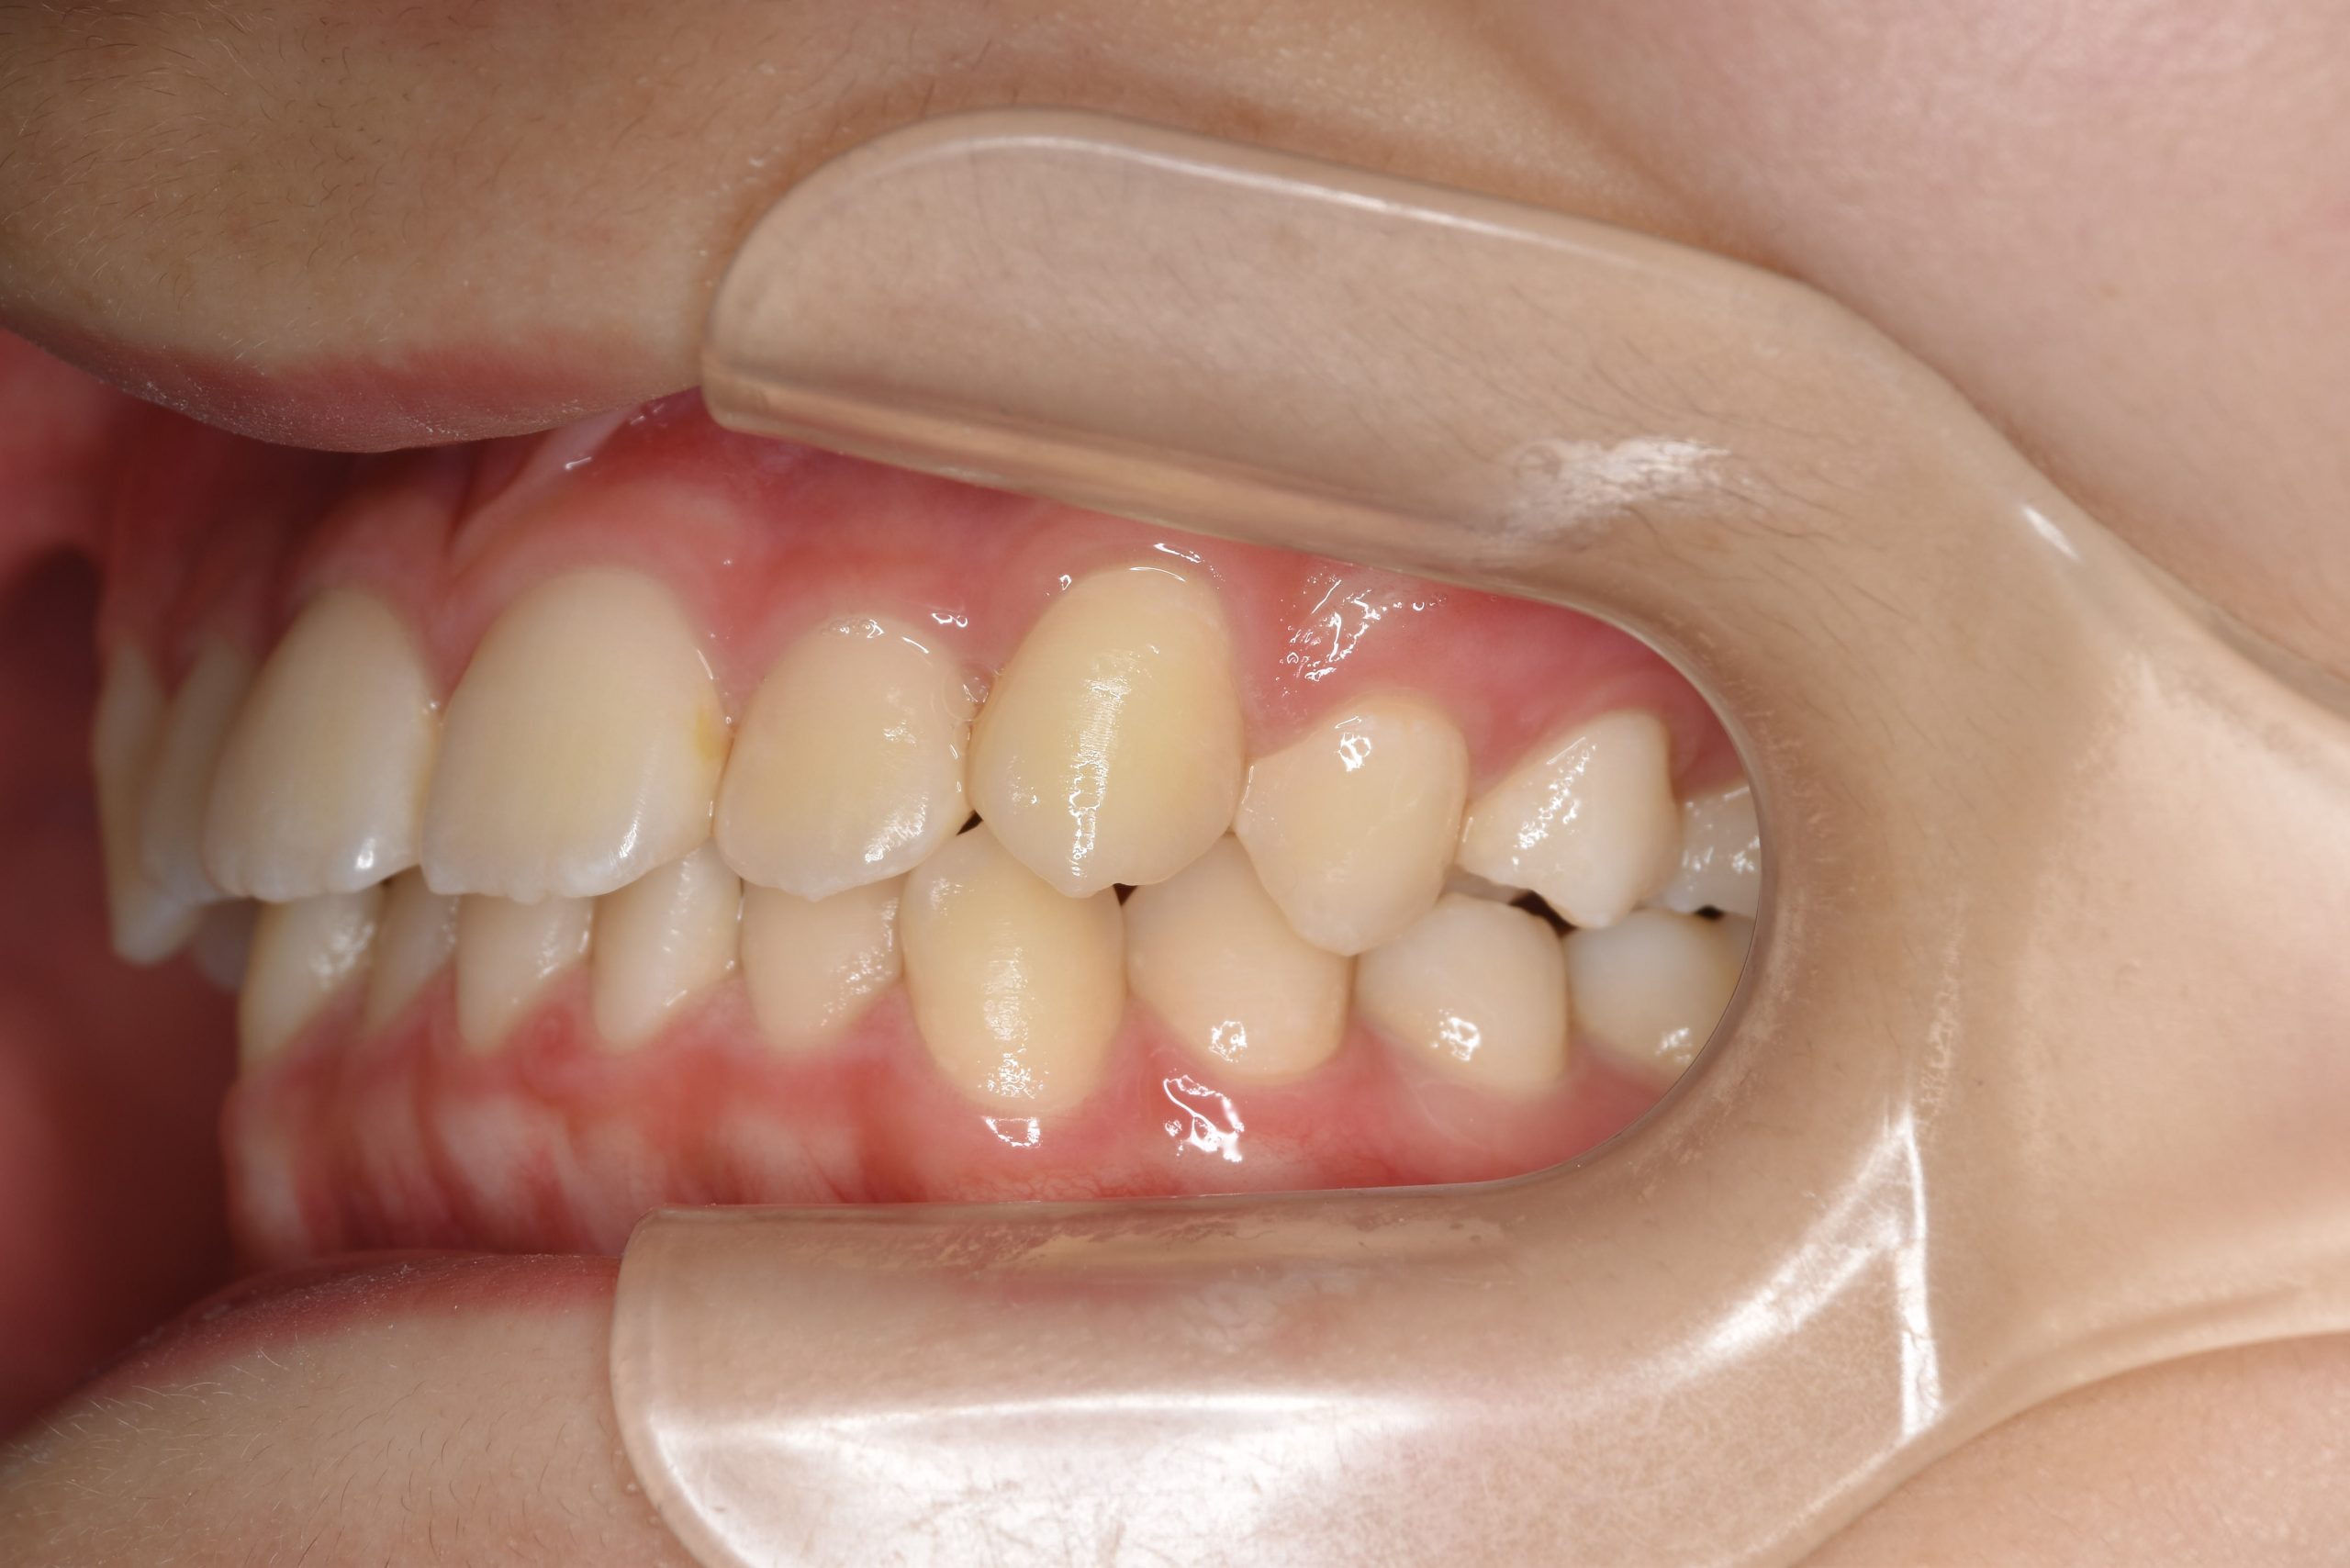

アフター

全顎ワイヤー矯正 症例_185

主訴 歯並び|横から生えている大人の歯

施術内容 小児矯正1期治療

治癒期間 4年間

費用 522,960円(税込)